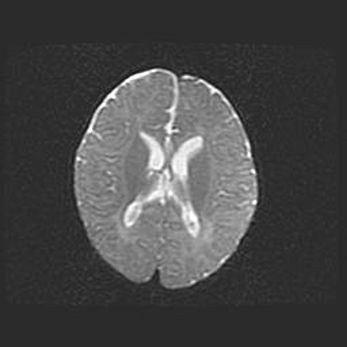

Церебральная ишемия II.

Возраст: 5 дней

Вес: 3400 г

Пол: женский

Окружность головы: 35 см

Срок гестации: 39 недель

Церебральная ишемия – это заболевание, характеризующееся недостаточностью (гипоксией) либо полным прекращением (аноксией) снабжения мозга кислородом по причине закупорки одного или нескольких сосудов. Это приводит к  что метаболическим расстройствам различной степени тяжести в тканях головного мозга, развитию коагуляционных некрозов и гибели нейронов.